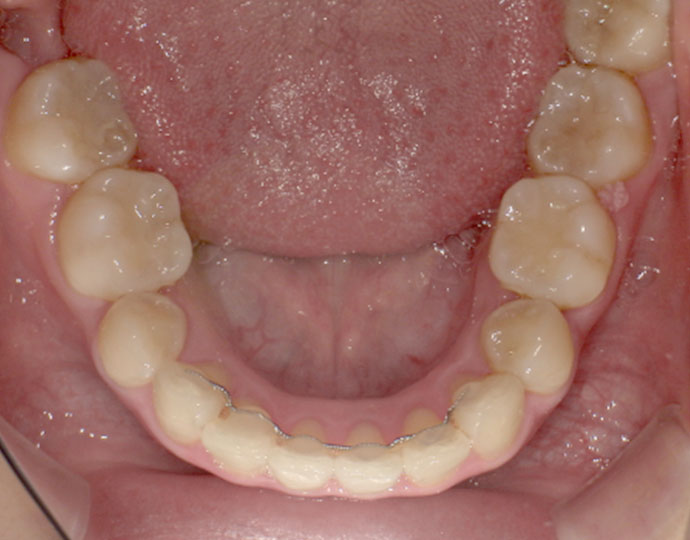

ワイヤー治療 叢生+上顎前突不正咬合 治療例

| 患者様 | 女性 19歳 |

| 主訴 | 歯並びと口元を綺麗にしたい。 |

| 診断 | 叢生歯列を伴う上顎前突不正咬合 |

| 治療方針 | 上顎左右第一小臼歯、下顎左右第二小臼歯の抜歯 |

| 治療に使用した装置 | セルフライゲーションブラケット インプラントアンカースクリュー×2 |

| 治療期間 | 2年6カ月 |

| 治療回数 | 24回 |

| 治療費(自費診療) | 880,000円(税込み) |